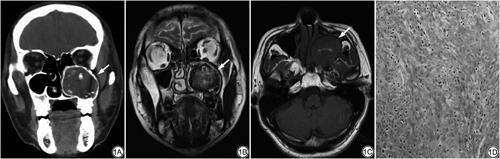

患者男,44岁,无明显诱因出现持续性鼻塞1年,睡眠时加重,入延边大学附属医院就诊。查体:鼻外形如常,鼻中隔居中,左侧鼻腔狭窄,鼻窦区无压痛,未见异常分泌物及新生物。CT示:左侧上颌骨见4.6 cm×4.5 cm×5.0 cm大小软组织肿块影,呈膨胀性生长,填充上颌窦,其内见散在骨嵴,周围有硬化骨质包绕,边界清楚(图1A)。MRI:肿块边界清楚,信号不均匀,T1WI呈等信号,内见斑片状高信号;T2WI呈高低混杂信号,硬化边缘呈低信号(图1B、1C)。手术所见:全麻下行左侧上颌窦探查肿物切除术,术中可见左上颌窦充满质地坚硬的蛋壳样肿物,内有质地较硬的肿瘤组织,伴有囊性液体,大小约4.5 cm×5.0 cm×6.0 cm,肿瘤与周边组织界限清楚。用剥离器将肿物全部切除。组织切面呈暗红色,内有出血,质地中等,并有完整的纤维包膜,无转移灶。病理:镜下见梭形的成纤维细胞呈漩涡状排列,其间有少量的泡沫细胞,间质内有少量出血(图1D)。病理诊断:左侧上颌骨非骨化性纤维瘤。术后随访3个月,未见复发征象。

非骨化性纤维瘤(nonossifying fibroma,NOF)为一种少见的骨结缔组织来源的良性肿瘤,无成骨倾向,发病率低,多见于青少年男性[1]。长骨干骺端为其好发部位,尤以股骨和胫腓骨多见。目前国内未见发生于上颌骨的报道,根据发病部位分为皮质型与髓质型,后者较少见。皮质型好发生在长骨干骺端的骨皮质内或皮质下,偏心性生长,边界清楚;髓质型则好发于细长管状骨及不规则骨,呈中心性生长,二者均可累及骨干[2]。CT表现为低密度肿块,边缘硬化,病灶内可有骨嵴,而无死骨。MR表现为T1WI呈等低信号,T2WI信号混杂,主要表现为低信号。本例CT表现为膨胀性生长,边界清楚的低密度肿块,其内见骨嵴,骨性包壳较厚;MR上T1WI呈等信号,其内斑片状高信号提示肿瘤内有出血,与组织病理检查结果相符合,T2WI呈高低混杂信号。分析本例影像学表现应与骨化性纤维瘤及上颌骨骨纤维异常增殖症鉴别,前者青少年女性多见[3],颌面部多见,影像上可见单房或多房膨胀性生长的等、高密度肿块,边缘清楚,其内夹杂形态不规则的骨化影,有成骨现象,这是本病的特征[4]。后者为一种慢性疾病,影像上可见病变范围较大,颌骨变形,骨密度增高,呈磨玻璃样改变,与正常骨无明显界限[5],故鉴别诊断并不困难。